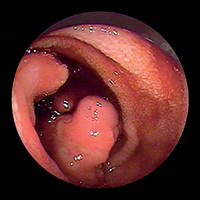

Немного по-другому выглядит ситуация с показаниями к капсульной эндоскопии при других патологиях тонкого кишечника — несомненна ее польза в диагностике различных полипозов (FAP-Syndrom (семейный наследственный полипоз), Peutz — Jaghers Syndrom) в первую очередь для планирования дальнейшей лечебной тактики и решения вопроса о необходимости хирургического вмешательства. Аналогичные показания касаются и пациентов с болезнью Крона, хотя в этом случае необходимо считаться с опасностью наличия стенозов и свищей — одного из наиболее частых ее осложнений, — являющихся прямым противопоказанием к капсульной эндоскопии. Для таких случаев была специально разработана Patency-Капсула, оболочка которой частично растворяется под влиянием кишечного содержимого — в результате к концу исследования она превращается в мешочек с соответствующим содержимым и может беспрепятственно преодолеть все стенозы и спайки. Насколько это, несомненно, оригинальное, но и не менее дорогостоящее решение найдет широкое признание в эндоскопической практике — вопрос времени. Достаточно шаткими являются и показания к капсульной эндоскопии в диагностике опухолей, и главным лимитирующим фактором здесь выступает уже упомянутая выше невозможность биопсии.

И именно в таких случаях помочь гастроэнтерологу и хирургу призвана еще более современная методика — двухбаллонная энтероскопия, называемая на Запа-

де еще «Push-and-Pull-Enteroskopie» (PPE). Уже из названия становится понятным и сам принцип этого предложенного в 2001 г. японцами (Yamamoto H. et al., 2001) и впервые в 2003 г. примененного на Западе исследования. Передвижение по тонкому кишечнику телескопически выдвигаемого зонда длиной около двух метров, состоящего из непосредственно энтероскопа и наружного зонда большего диаметра, осуществляется путем «нанизывания» на эндоскоп кишки, что становится возможным за счет периодического раздувания и перемещения относительно друг друга двух баллонов, один из которых находится непосредственно на конце эндоскопа, а другой — на конце наружного зонда. Так как по структуре своей двухбаллонный энтероскоп является обычным эндоскопом, он обладает и всеми его

преимуществами — возможностью промывать оптику во время исследования (что особенно ценно при диагностике кровотечений), проводить биопсии и, самое главное, осуществлять эндоскопические вмешательства. Именно поэтому зачастую капсульная эндоскопия (естественно, при положительном результате) дополняется двухбаллонной энтероскопией. Введение энтероскопа, как правило, осуществляется перорально ортоградно, только в редких случаях (например, при недостаточной инспекции кишечника или выявленной во время капсульной эндоскопии локализации источника кровотечения в дистальных отделах тонкого кишечника) необходимо дополнительное проведение ретроградной трансанальной энтероскопии. Длительность исследования составляет в среднем два часа, естественно, без внутривенного наркоза (как правило, хватает обычной седоанальгезии) тут не обойтись.